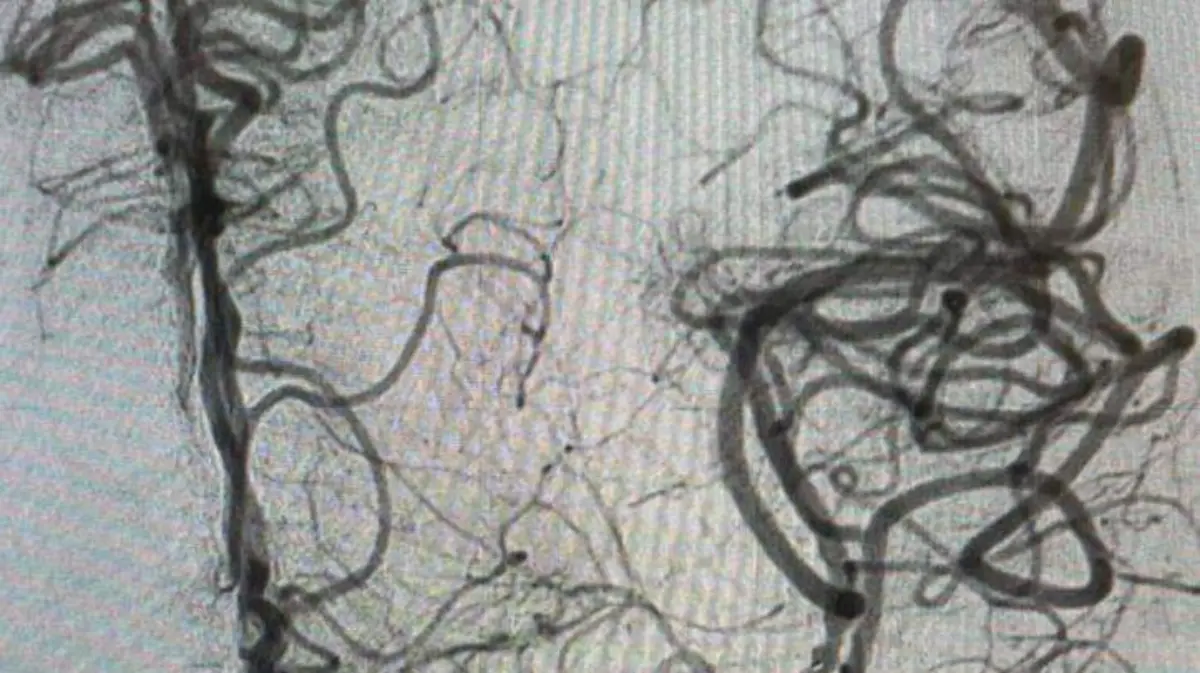

Para atender este caso, se le practicó una resonancia magnética; se le detectó la obstrucción de una arteria por un coágulo; y fue identificada la zona de afectación".

Posteriormente, se efectuó el rescate, para lo cual procedieron a introducir catéteres de la ingle hasta el cerebro.